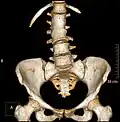

Several congenital block vertebrae in the transition from the thoracic to the lumbar spine and hemivertebrae. -

Congenital block vertebra in the lumbar spine (partial vertebrae 3 and 4). The rear portion of the disc still exists. -

Congenital block vertebra of the lumbar spine. CT volume rendering. -

Congenital block vertebra of the lumbar spine. CT volume rendering.